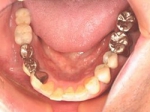

術後(鏡像)

術後口腔内(正面観)もう入れ歯は要らなくなりました。